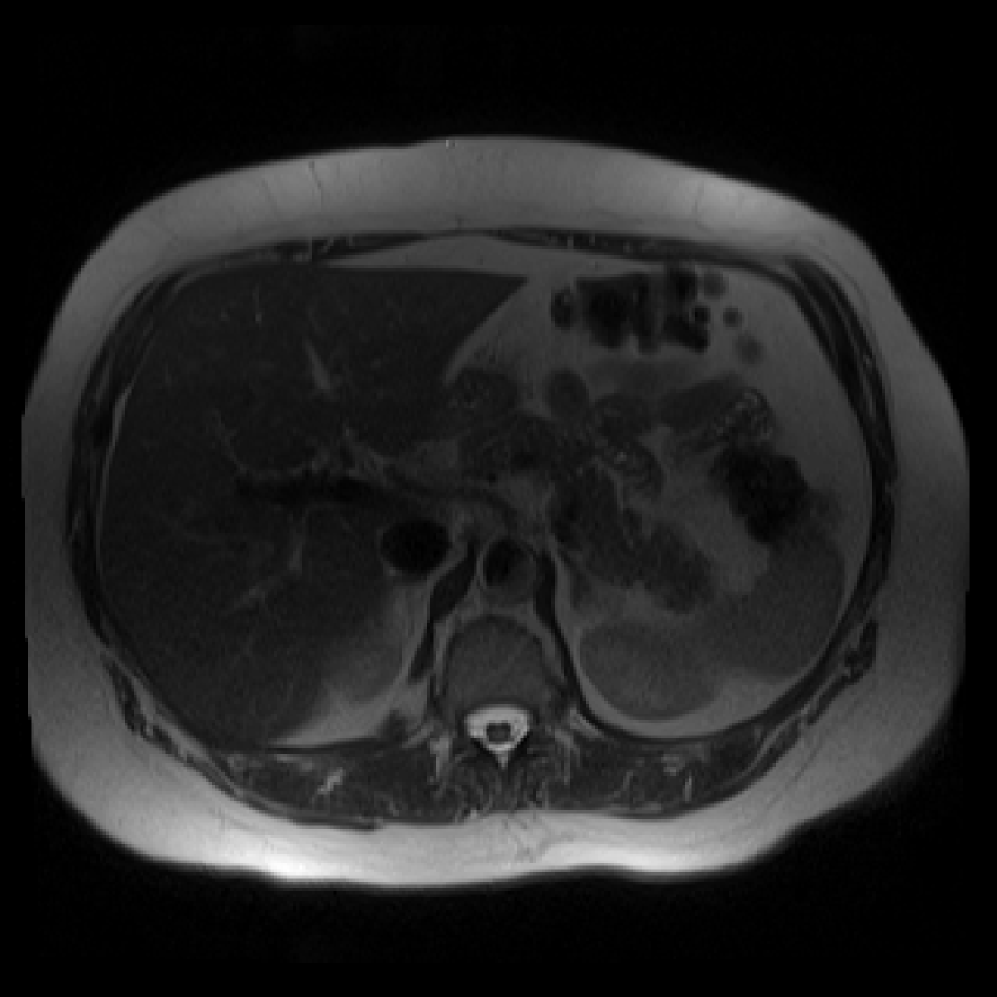

Accurate pancreas segmentation is a critical prerequisite for precise cyst analysis and classification. Recently, we developed PanSegNet [zhang2025large], a novel segmentation architecture incorporating linear self-attention layers [zhang2022dynamic] within the nnUNet framework [isensee2021nnu] to enhance global information modeling capabilities while maintaining computational efficiency (Fig. 1). PanSegNet demonstrated exceptional segmentation performance across both T1W and T2W modalities, achieving mean dice scores of 86.817.30% and 89.626.38%, respectively (Table 1, Fig. 2b-c). This performance significantly exceeded that of Swin-UNETR [hatamizadeh2021swin], one of the most used state-of-the-art transformer-based medical segmentation models, which achieved dice scores of 79.091.40% and 76.290.66% for T1W and T2W, respectively (). In this study, we integrated PanSegNet into our Cyst-X engine along with a classifier for risk prediction. In Section 2.2, we show that the choice of segmentation model affects the classification results. The performance advantage of PanSegNet was consistent across all seven medical centers, demonstrating robust generalization despite variations in imaging protocols and equipment (Table 1). This cross-institutional reliability is particularly important for clinical applications, where model performance must remain consistent regardless of imaging site or acquisition parameters.

![[Uncaptioned image]](x68.png)

Each patient was categorized into one of these three ground truth classes: no risk/control, IPMN low-risk, or IPMN high-risk. To evaluate variability in image acquisition, we applied uniform manifold approximation and projection (UMAP) to image quality indicators, revealing distinct clustering patterns by imaging center and slice thickness. This heterogeneity reflects real-world clinical variability, enhancing the dataset’s generalizability while presenting technical challenges for model development. Fig. 6 shows examples of low-grade, high-grade, and cancer developing IPMNs from the Cyst-X dataset.